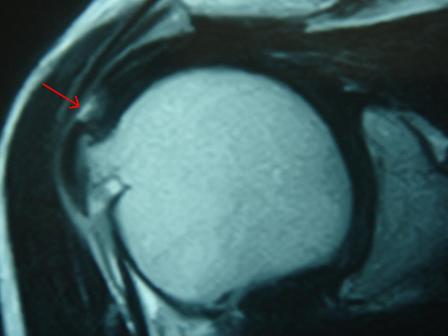

今はMRIで、ほんの小さな断裂も見つけられます。

図の矢印が断裂部分です。

腱板は肩甲骨の骨、肩峰(けんぽう)とぶつかって摩擦を繰り返すことで損傷が進みます。